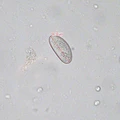

Bildquiz Antwort % Korrekt

Trichuris trichiura

100%